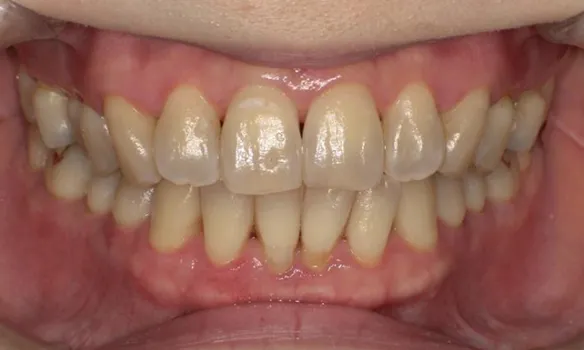

審美歯周病治療

見た目も美しく

歯周病治療を行うと歯茎が下がったとよく聞きます。残念ながら、炎症が長期に渡り存在していた歯茎や、重度歯周病では、治療を行うことにより歯茎が下がり炎症が除去されると歯茎が下がってしましやすいです。そういった場合、セラミックス治療を行うことで審美的に改善を図ることがあります。

また、歯周病はないのに、歯茎が下がってしまうことによる審美性が損なわれてしまう病気があります。そのような場合、歯茎の移植などを行うことにより、歯を削ることなく審美性を改善させることができます。 -